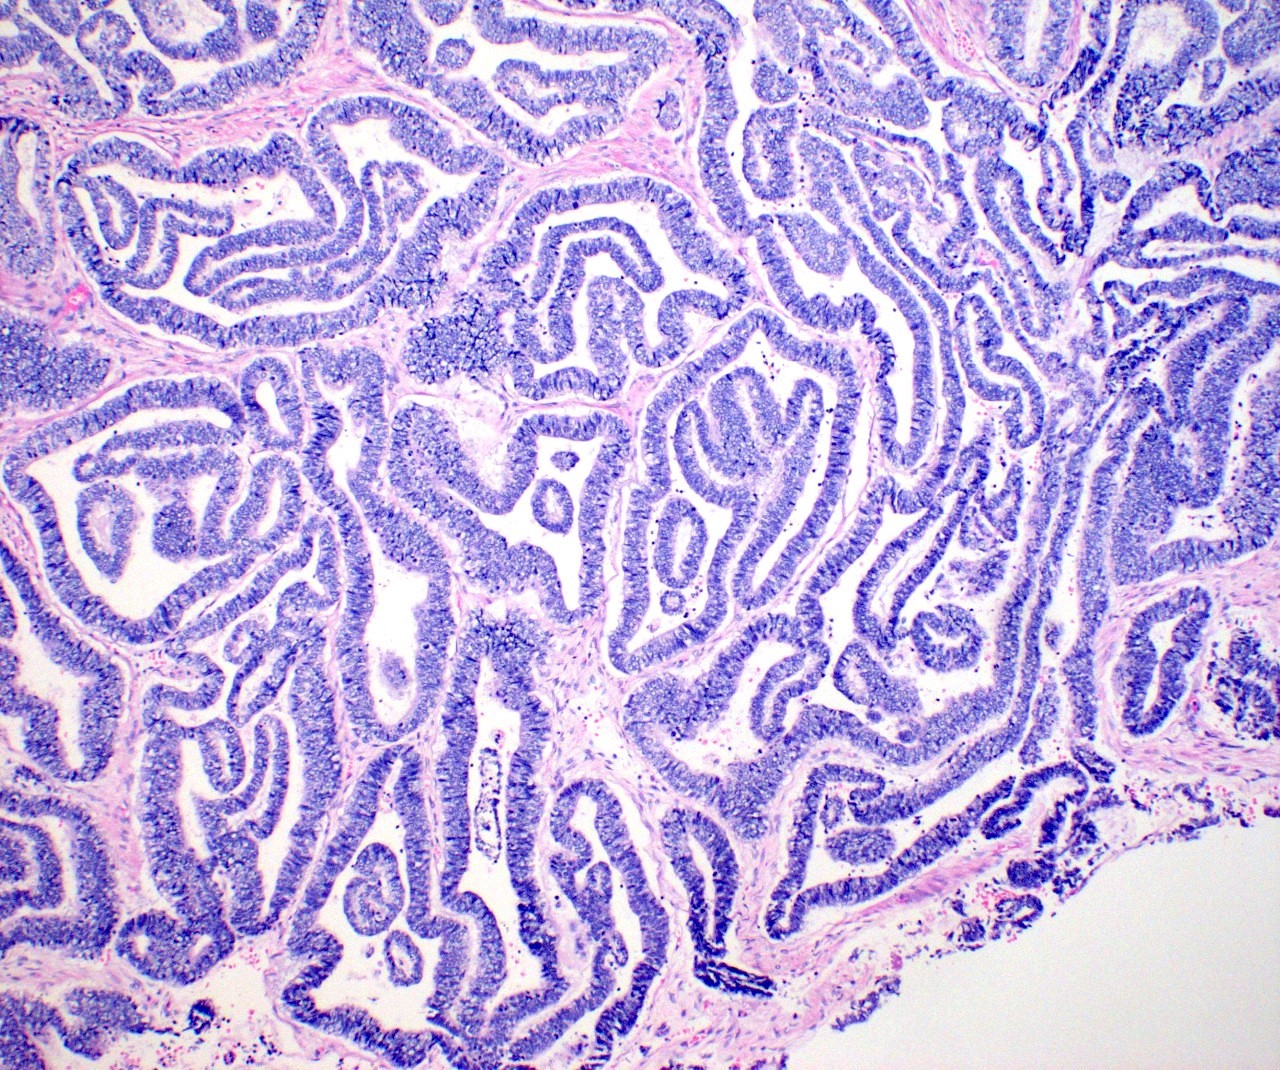

- Variety of histologic patterns that may be present within the same tumor

- Most frequently small tubules with ductal / glandular growth

- Papillary, solid growth, trabecular, retiform, sex cord-like, sieve-like, glomeruloid and spindle cell areas have all been described

- Luminal eosinophilic secretions are characteristic but not always identified

- Tumor cells can be flattened, cuboidal or columnar with mild to moderate cytological atypia

- Clear cell features can be seen but are less common

- High grade cytological atypia is usually not a predominant feature

- Nuclei show vesicular chromatin and nuclear grooves

- Sarcomatoid transformation has been seen in rare instances

- Squamous, ciliated or mucinous differentiation (metaplasia) are not present and there are no associated mesonephric remnants (J Clin Med 2021;10:698)

Microscopic (histologic) images

Contributed by Daniel Graham, M.D., Adele Wong, M.B., B.Ch., B.A.O. and Lucy Ma, M.D.